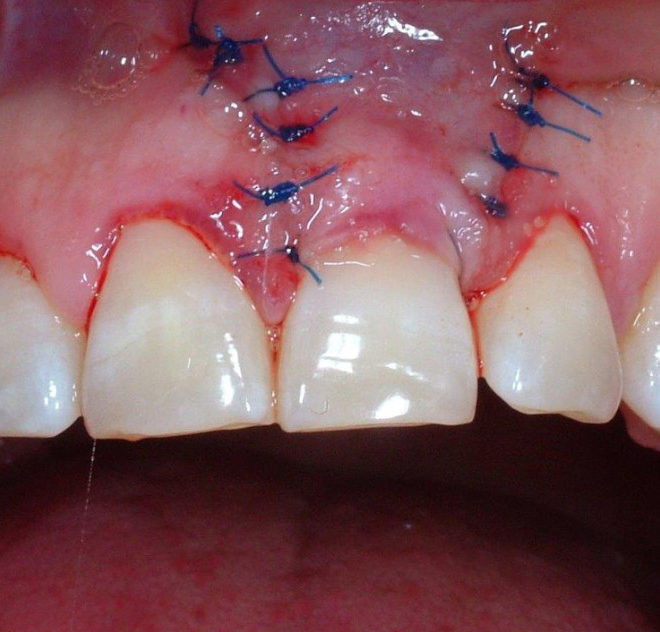

L’ODONTOIATRIA, come molte altre discipline chirurgiche, ha da alcuni anni attuato una vera e propria rivoluzione nell’approccio verso una vasta quantità di patologie a largo impatto epidemiologico, approccio fondato sull’utilizzo di nuove tecniche che si adeguano alla biologia tissulare.

La mini-invasività è quindi mirata all’utilizzo di un nuovo concetto di chirurgia, definito “biosurgery”, cioè rispetto delle capacità dell’organismo a ritrovare, correttamente indirizzato,spontanee e più efficaci guarigioni.

Essa non va pertanto intesa in senso di minore radicalità chirurgica, ma nel senso di ridurre le complicanze legate a vie di accesso o tecniche più traumatiche. Le nuove tecnologie usate oggi sono: Laser, Radiofrequenze, , Fibre ottiche, L, Microscopio chirurgico, Debrider o Shaver.